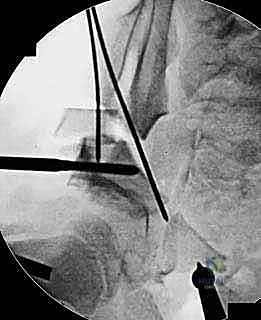

باستخدام أدوات خاصة، يقوم الدكتور هطيف بتدوير التجويف الحقي الحر في ثلاثة أبعاد (للأمام، وللخارج، وللأسفل) حتى يغطي رأس عظم الفخذ بشكل مثالي وميكانيكي سليم. يتم التحقق من الزاوية الجديدة فوراً داخل غرفة العمليات باستخدام جهاز الأشعة السينية المتحرك (C-arm).

5. التثبيت القوي (Fixation)

بمجرد الوصول إلى الوضع المثالي، يتم تثبيت العظام في مكانها الجديد باستخدام براغي معدنية قوية من التيتانيوم أو دبابيس (K-wires). هذا التثبيت يضمن التحام العظام بشكل صحيح خلال فترة التعافي.

* يتم أخذ صور أشعة سينية للتأكد من بدء التحام العظام (Callus formation).